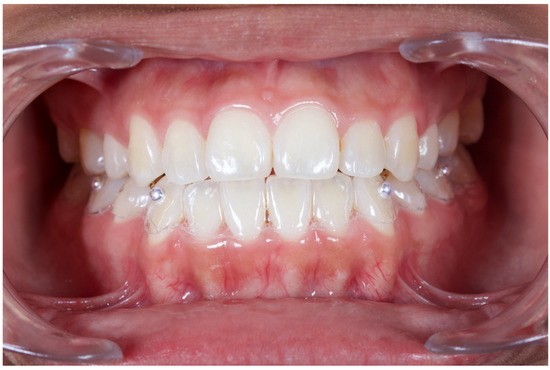

2. Materials and Methods